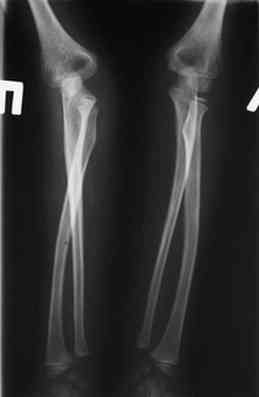

Иллюстрация к лечению застарелого повреждения Монтеджиа

Пациентка клиники детской травматологии ЦИТО

На рентненграмме видна деформация локтевой кости на границе верхней и средней трети. Ведь там был перелом.

Колеги!!! Сконцентрируйтесь... Не спешите и подумайте, что препятствует головке луча вернуться на свое место??? Отвыкание :):):) Конечно нет. Внимательно посмотрите на ось локтевой кости. Как раз она мешает вернуться лучу на место. Зря Монтеджи старался, что ли???

Многоуважаемые коллеги, всем большое спасибо!!! Да, здесь было повреждение Монтеджиа, когда нарисовал скиаграмму все стало понятно. Мне очень понравились рекомендации Константина Требухина, только немножко видоизменил; я считал так, если деформацию исправить то локт/кость должна удлиниться, и во вторых, если на аппарате низвести лучевую кость, то может наступить позиционное несоответствие в дистальном радиоульнарном сочленении. 28.02.08г операция - шарнирная остеотомия локтевой кости на уровне деформации, далее вскрыт плечелучевой сустав, удалены рубцовые тканы, после исправления варусной деформации и создания физиологического изгиба локтевой кости головка луча легко вправился, из части рубцовой ткани сделана пластика кольцевндной связки, трансартикулярная фиксация спицей, локтевая кость двумя спицами.